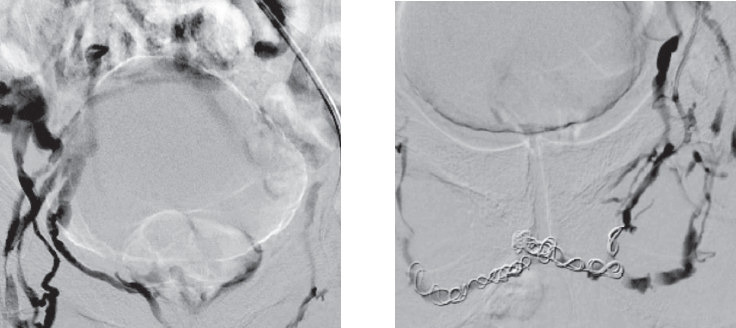

Ретроградная рентгенохирургическая эмболизация простатического сплетения доступом через v. basilica (трансбазилярный доступ) является, с нашей точки зрения, более удобной, так как при ней отсутствует изгиб внутрисосудистого катетера в илеокавальном сегменте (рис. 8).

Рис. 8. Ретроградная рентгенохирургическая эмболизация простатического сплетения доступом через v. basilica (трансбазилярный доступ). Слева контрастируется простатическое венозное сплетение и кавернозные тела полового члена в месте патологического венозного дренажа, справа — отсутствие венозной утечки после эмболизации спиралями Gianturko (Cook Medical, USA)

Fig. 8. Retrograde X-ray guided surgical embolization of the prostatic plexus by access through v. basilica (transbasilar access). On the left, the prostatic venous plexus and cavernous bodies of the penis in the place of pathological venous drainage are contrasted, on the right – the absence of venous leakage after embolization with Gianturko spirals (Cook Medical, USA)